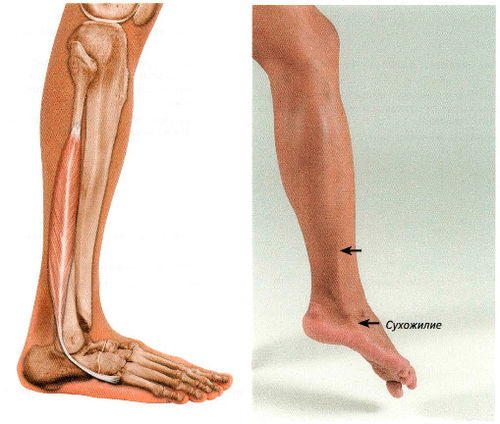

Анатомия голеностопа: Сухожилия и их строение